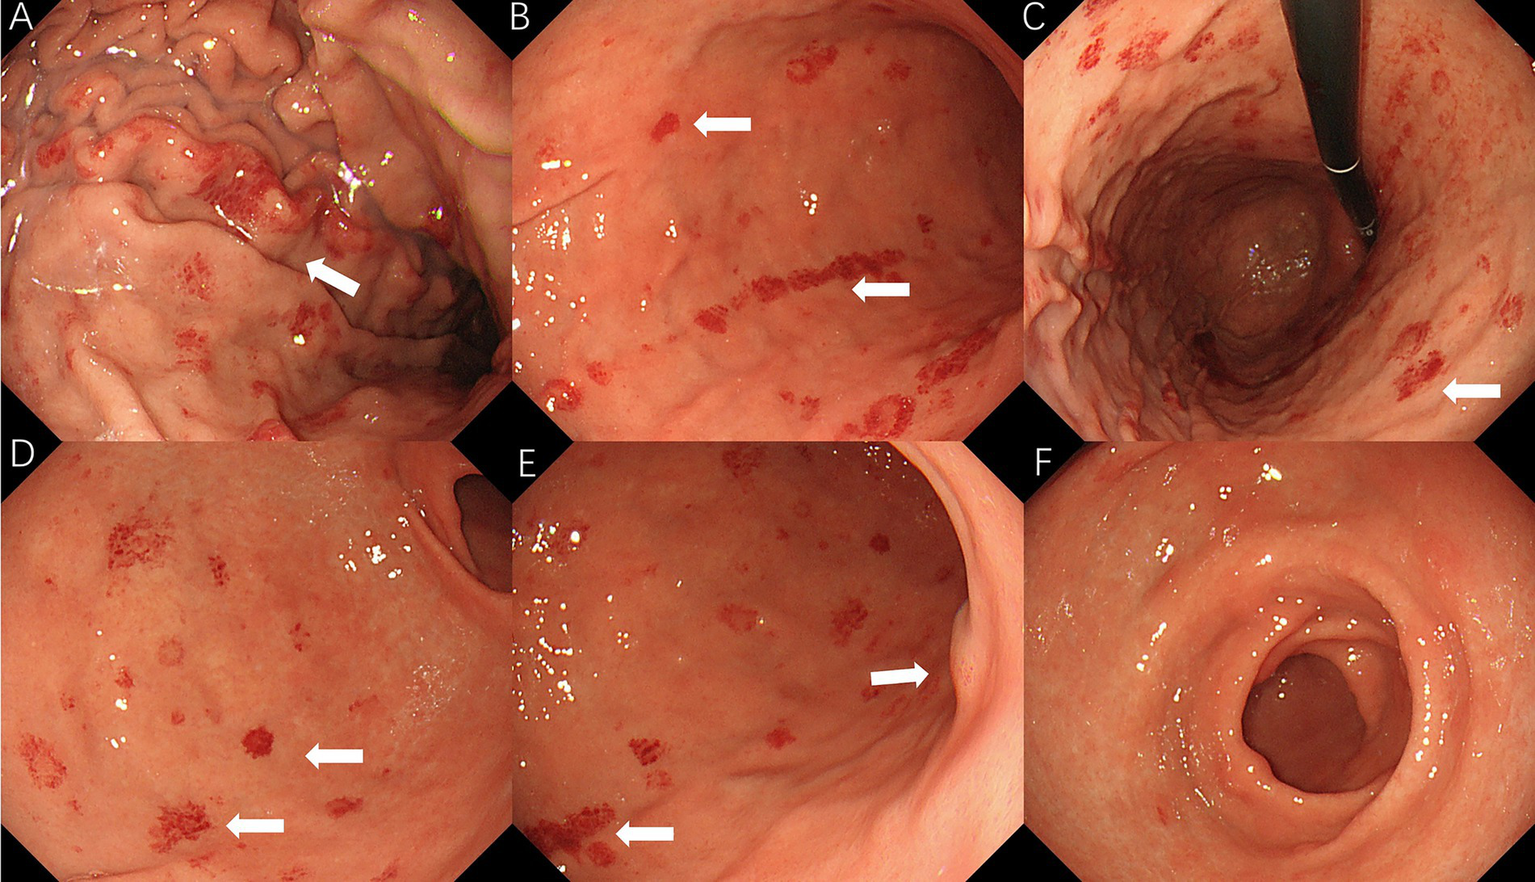

A 64-year-old man presented to the ear, nose, and throat (ENT) department on 17 April 2023, with a several-month history of hoarseness, sore throat, and coughing with sputum production. The patient had a history of hypertension for 20 years and was on long-term antihypertensive therapy with 80 mg of valsartan and 50 mg of losartan. He had a 50-pack-year smoking history (10 cigarettes per day) and had never attempted to quit. There was no notable family history of disease. Physical examination revealed normal vital signs, chronic congestion of the pharyngeal mucosa, and mild bilateral tonsillar enlargement (Grade 1) without erythema or suppuration. Laboratory tests showed a hemoglobin level of 111 g/L and C-reactive protein (CRP) of 53.56 mg/L. Chest CT revealed a subpleural lesion in the left lung, suggestive of chronic inflammation, with follow-up recommended after treatment. Mild thickening and blurring of the esophageal wall prompted further evaluation. Flexible laryngoscopy revealed mild lymphoid follicular hyperplasia in the posterior pharyngeal wall, without swelling or erythema of the epiglottis, and slight edema and polypoid growth in the anterior parts of both vocal cords. The clinician suspected an upper respiratory infection and prescribed oral cefuroxime axetil for treatment. Due to the thickening of the esophageal wall seen on CT imaging, tumor markers for esophageal cancer were tested, revealing an elevated squamous cell carcinoma (SCC) antigen level of 1.84 ng/mL, which prompted an immediate upper gastrointestinal endoscopy. The endoscopic examination revealed diffuse redness with scattered red erythema and sticky mucus in the gastric lumen. Notably, the regular arrangement of collecting venules (RAC) in the gastric angle was absent (Figures 1A–C), and scattered erythematous spots were also observed in the duodenum (Figure 1D). Based on these findings, the initial diagnosis was Helicobacter pylori-associated gastritis. The endoscopist performed a routine biopsy from the gastric antrum, and the pathological examination showed mild chronic superficial gastritis. Both Helicobacter pylori pathology testing and the 13C urea breath test were negative. Congo red staining was not performed on the initial biopsy specimens. After receiving anti-inflammatory medications, the patient’s upper respiratory tract infection symptoms improved, and he did not return for further follow-up.

Figure 1

Initial endoscopic findings: (A) diffuse redness with scattered red erythema; (B) diffuse redness with sticky mucus in corpus; (C) RAC visible in body; and (D) duodenal erythematous spots.

On 10 April 2025, the patient underwent repeat endoscopy due to new-onset gastroesophageal reflux symptoms. The endoscopy revealed disc- and linear-shaped erythema in the gastric body with abnormally bright reddish coloration (Figures 2A–D). A submucosal tumor (SMT)-like protrusion was observed in the posterior wall of the lower gastric body (Figure 2E). In contrast, the gastric antrum showed no visible erythema (Figure 2F). Biopsy samples from these lesions showed eosinophilic deposits in the lamina propria (Figure 3B). Congo red staining was weakly positive, and apple-green birefringence under polarized light confirmed amyloid deposition (Figure 3C). Retrospective review of the 2023 biopsy revealed previously overlooked eosinophilic deposits (Figure 3A).

Figure 2

2025 endoscopic findings: (A–D) disc/linear gastric erythema; (E) SMT-like protrusion; and (F) antrum without erythema.